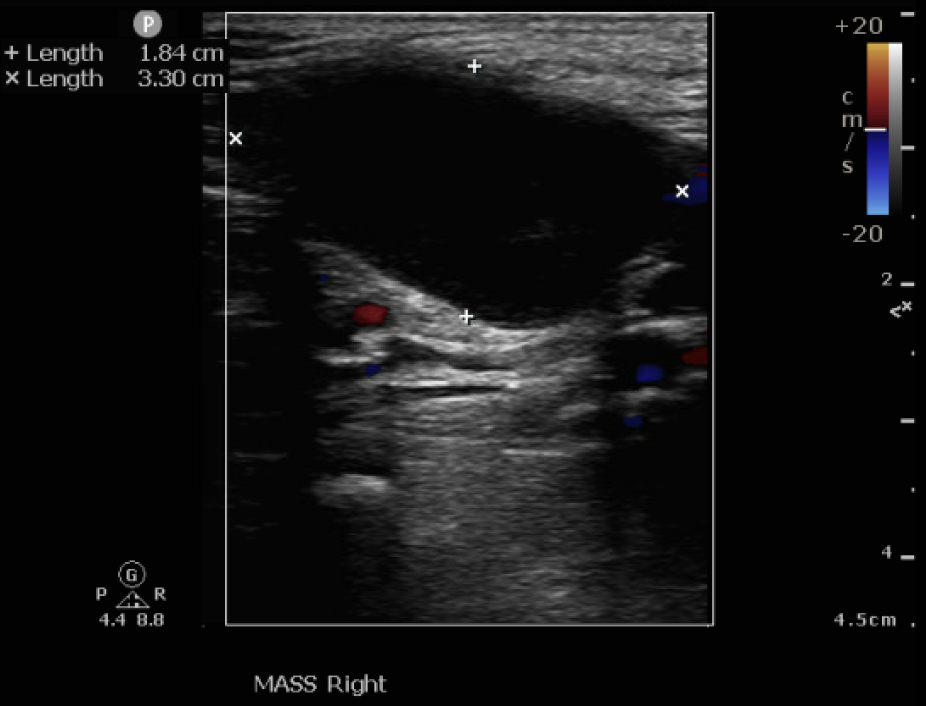

Relevant Test Results Prior to Catheterization

Lab data showed leukocytosis and significantly elevated C-Reactive Protein, alongside deteriorated renal function. Vascular Duplex showed monophasic flow and a hematoma near the Common Femoral Artery (CFA). CTA revealed Severe PAOD via extensive total occlusion from the right right External Iliac Artery (EIA) to the Superficial Femoral Artery (SFA), and a thrombosed aneurysm at the femoral bifurcation, and extensive Deep Venous Thrombosis (DVT) extending from the femoral vein distally.

The procedure utilized a hybrid retrograde and antegrade approach. Retrograde access was established via a micropuncture kit under angiography guidance into the distal Superficial Femoral Artery (dSFA), but wiring attempts failed due to an intervening aneurysm, necessitating a switch to the antegrade route from the left brachial artery. A wire escalation technique, assisted by a microcatheter, successfully crossed the extensive CTO, and was met with retrograde microcatheter and externalized via the dSFA puncture site (retrograde access), establishing through-and-through wire access. Following initial balloon predilation and IVUS confirmation of diffuse thrombus, extensive angioplasty was performed. Definitive treatment involved deploying multiple overlapping GORE¢ç VIABAHN¢ç Endoprosthesis diameters (from 6mm to 8mm) from the dSFA proximally to the pEIA via left femoral access, effectively treating the long occlusion and excluding the aneurysm. A COOK Zilver Flex iliac stent reinforced the proximal landing zone. The stented segment was rigorously post-dilated up to 12 atm. The procedure concluded with a Drug-Eluting Balloon (DEB) PTA (BOSTON Ranger Paclitaxel-Coated PTA Balloon Catheter) to the dSFA to mitigate restenosis in the non-stented region. Final angiography confirmed good flow without distal embolization.